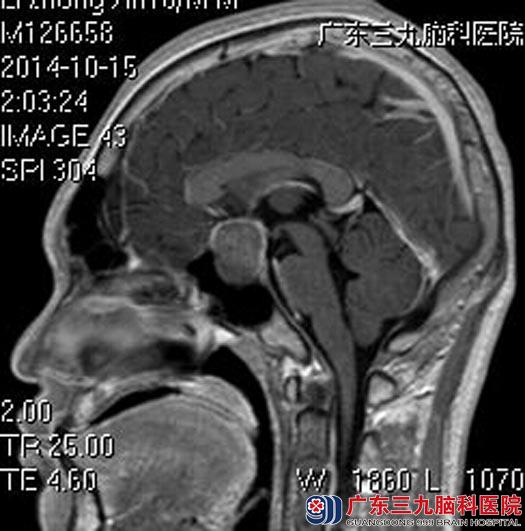

为进一步确诊,小李在父母的陪同下来到广东三九脑科医院垂体瘤诊疗中心,头颅MRI检查提示:鞍内及鞍上示一不规则异常信号影,大小约26mm×22.4mm×27.1mm。视交叉受压稍上抬,内分泌检查结果提示生长激素159ng/ml,初步考虑垂体腺瘤。